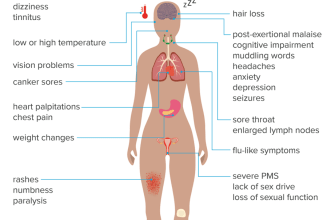

Joint stiffness refers to the sensation of difficulty or resistance when moving a joint. It can be accompanied by pain, swelling, and a decreased range of motion. Joint pain, on the other hand, is the discomfort or ache experienced in and around a joint. Both joint stiffness and pain can be acute or chronic, with chronic joint pain lasting for more than three months.

1. Arthritis: Arthritis is a common cause of joint stiffness and pain. Osteoarthritis, the most prevalent form, occurs when the protective cartilage that cushions the ends of bones wears down over time. Rheumatoid arthritis, an autoimmune disease, causes joint inflammation and can lead to chronic joint pain.

2. Injuries: Joint stiffness and pain can also result from injuries such as sprains, strains, or fractures. These injuries can damage the structures within the joint, including ligaments, tendons, and cartilage.

3. Overuse: Repetitive movements or excessive strain on a joint can cause inflammation and subsequent stiffness and pain. This is commonly seen in athletes or individuals with physically demanding occupations.

4. Infections: In rare cases, joint stiffness and pain can be caused by infections, such as septic arthritis. This occurs when bacteria or viruses enter the joint, leading to inflammation and discomfort.